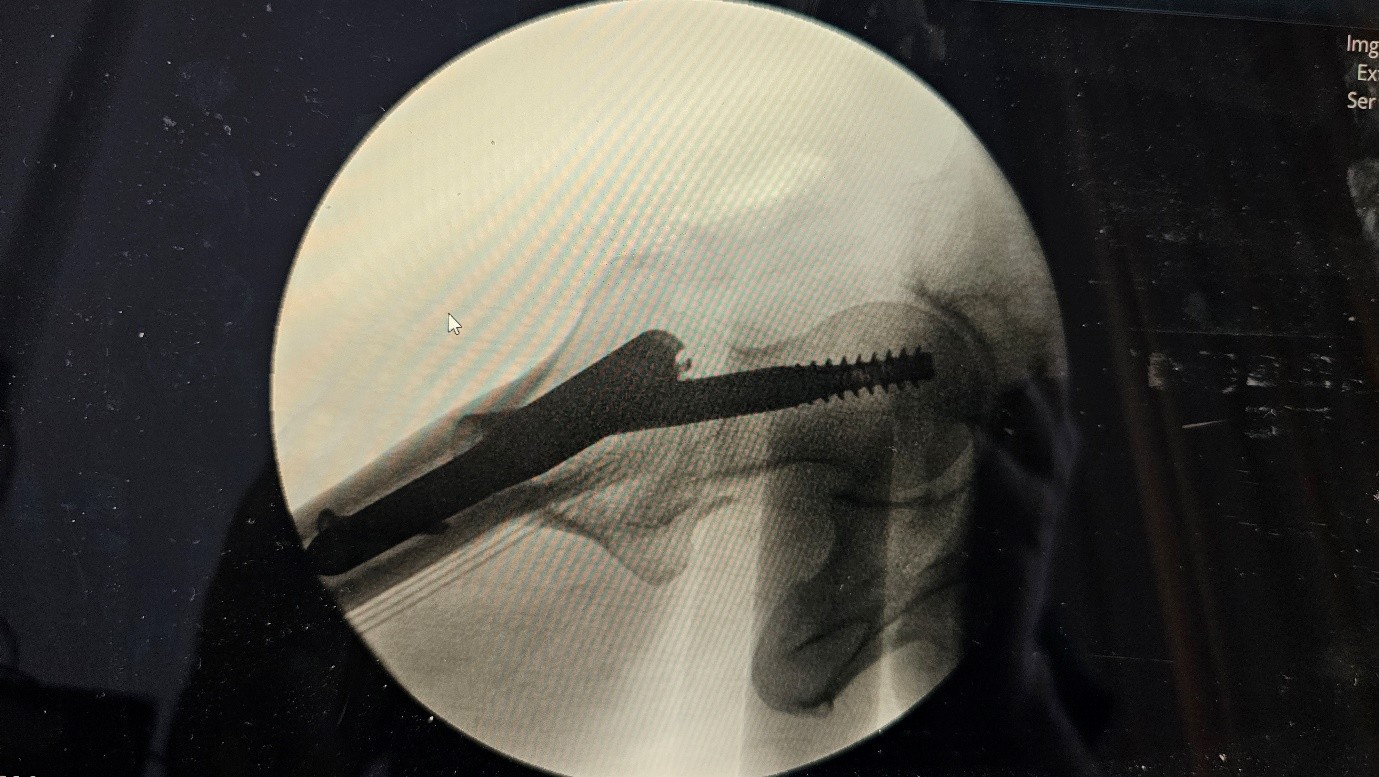

The patient underwent internal fixation using a Trochanteric Fixation Nail Advanced (TFNA). Intraoperatively, fracture reduction was suboptimal, with mild varus malalignment. The entry point for the nail was slightly lateral, and the cephalic screw was inserted in an inferior-anterior position. Intraoperative fluoroscopy showed acceptable placement, although the exact position of the screw could not be fully assessed.

Postoperative X-rays were inconclusive due to suboptimal views. To evaluate screw position and fracture alignment more accurately, a CT scan was performed. The CT revealed that the cephalic screw had cut through the femoral neck, protruding medially outside the cortex, and continued into the femoral head—confirming a case of cut-through.

Post fall xray :

Fig 1

Fig 2

Figure 1

Figure 2